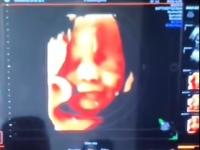

Bebê reage à voz do pai e sorri durante ultrassom em Xanxerê

A reação de uma bebê durante um exame de ultrassom no município de Xanxerê, no Oeste de Santa Catarina, viralizou na internet após o pai publicar o vídeo nas redes sociais do momento em que fala com a criança, ainda na barriga da mãe, e ela esboça um sorriso.

O médico que fez o exame na mãe Gislaine Sonaglio é Eduardo Guerra. O ultrassom foi realizado no dia 29 de julho, quando a bebê Laís Vitória estava com 33 semanas. “Com certeza, o bebê está escutando se a família conversar em casa [...]. Já tive situações parecidas, mas nunca como essa realmente. Foi algo impressionante", comenta.